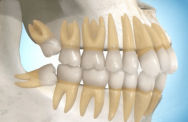

Radiografia mostrando 3º Molares

Possíveis posicionamentos de 3º molares